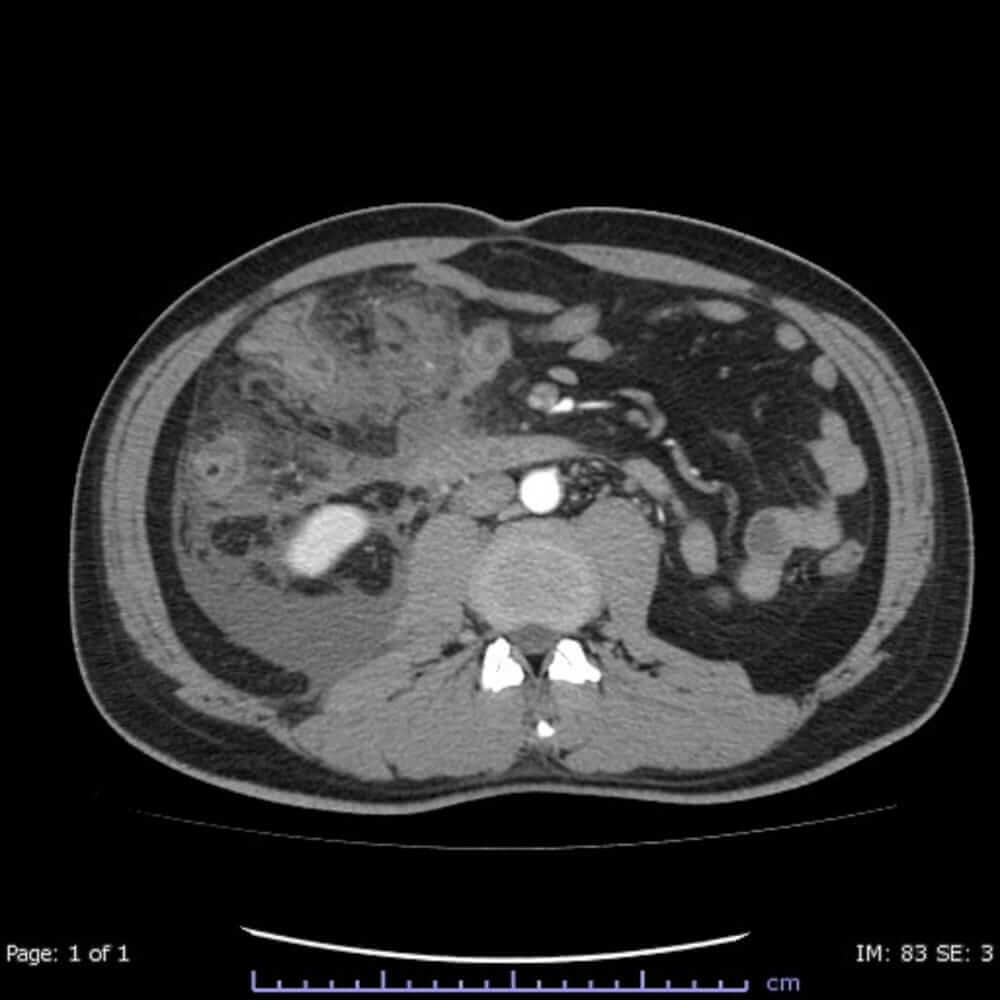

Londýn – Umělá inteligence je schopná zjistit míru agresivity sarkomu, vzácného typu nádorového bujení, ukázal nový klinický výzkum. Oproti laboratorním analýzám ji určuje s téměř dvojnásobnou přesností, píše britská BBC.

Podle pracovníků londýnské nemocnice The Royal Mardsen a Institutu pro výzkum rakoviny by to mohlo zlepšit léčbu tisíců lidí každý rok. Nástroj AI totiž dokáže rozeznat detaily, kterých si lidské oko není schopné všimnout. Umělá inteligence dosáhla při určování rakoviny 82% přesnosti v porovnání s 44% při klasické biopsii, tedy při odběru části tkáně a analýzy pod mikroskopem.

Britští vědci prováděli výzkum s radiologickými skeny 170 pacientů s retroperitoneálním sarkomem, typem rakovinového nádoru, který se vyvíjí v pojivové tkáni v zadní části břicha. Na základě těchto dat pak algoritmus umělé inteligence určoval závažnost podobných druhů nádoru u dalších 89 evropských a amerických pacientů.